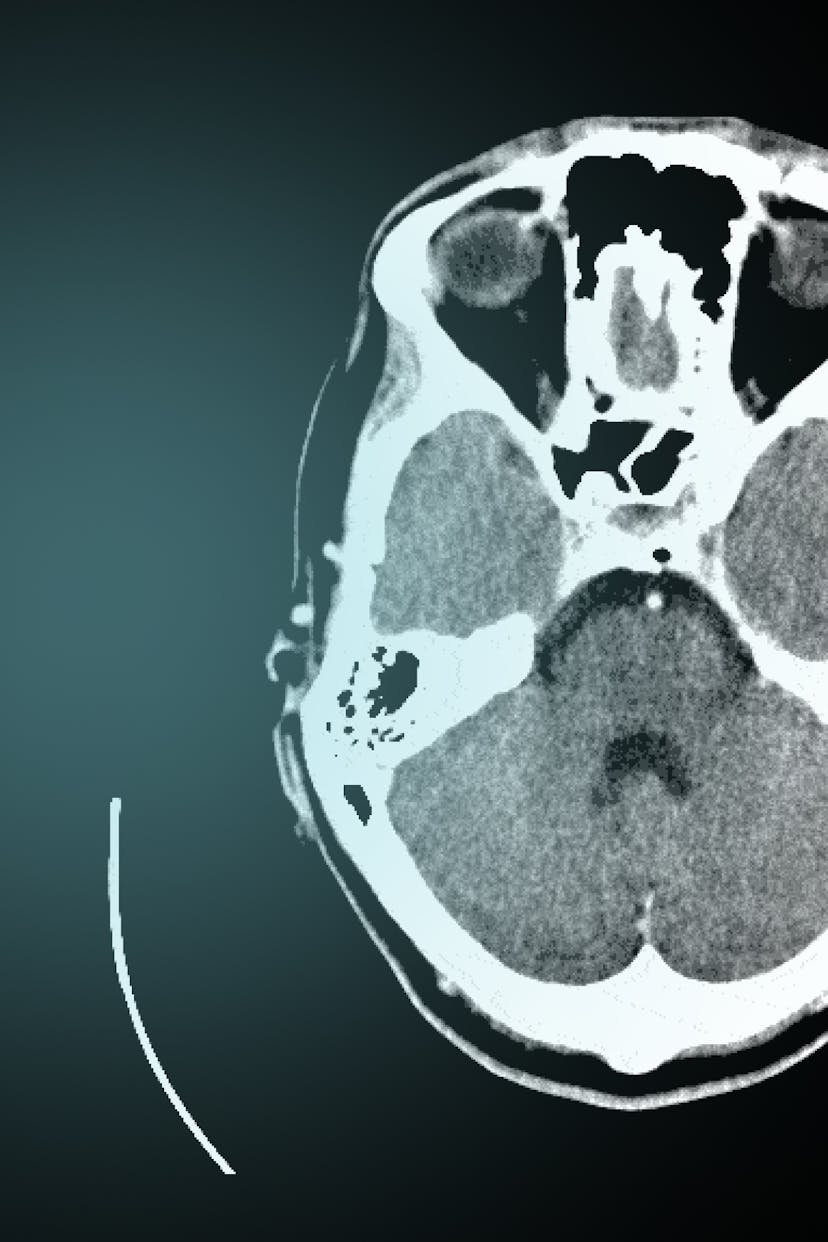

Coronial investigations into sudden, unnatural, violent and accidental deaths occupy an important role in the Australian legal system. They require coroners to ascertain the identity of the deceased, determine the cause of a death and in many instances, make recommendations for reducing the occurrence of preventable deaths. A key element of the Australian coronial investigation has been the invasive autopsy, which is performed by a forensic pathologist if a coroner deems it necessary for determining the medical cause of death. In recent decades, the autopsy has become a site of contestation, especially for families of the deceased who oppose post-mortem dissections due to religious or cultural beliefs. Since the late twentieth century, forensic imaging technology, particularly post-mortem computed tomography (CT), has offered the ideal of a non-invasive, permanent, virtual autopsy.

This project examines how forensic imaging technology impacts coronial investigations in Australia. It focuses on how post-mortem CT has been used since the late twentieth century to supplement or as a triage for invasive autopsies for the purposes of identifying the deceased and determining the medical cause of a death. Little is known about how technological modifications to death investigations assist or hinder practitioners in fulfilling their statutory responsibilities under coronial law. The project thus aims to analyse how forensic imaging technology has transformed coronial investigations since the twentieth century and how it continues to affect the way coroners, pathologists, radiologists and other medico-legal personnel working in the jurisdiction perform their roles in the legal system. If the use of post-mortem CT is to be expanded in Australia, then it is critical to these debates that we examine the social and legal effects of the implementation of forensic imaging technology in coronial investigations.